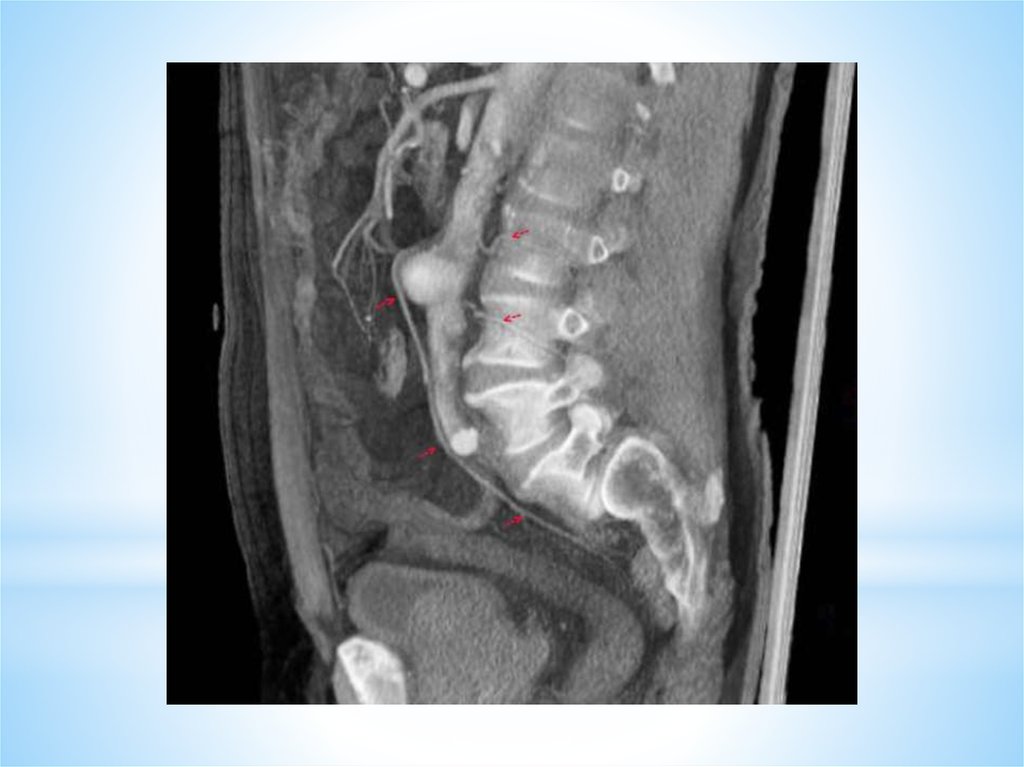

МРТ диагностика изменений межпозвонковых дисков

Рентгенологическая диагностика патологии сердечно-сосудистой системы